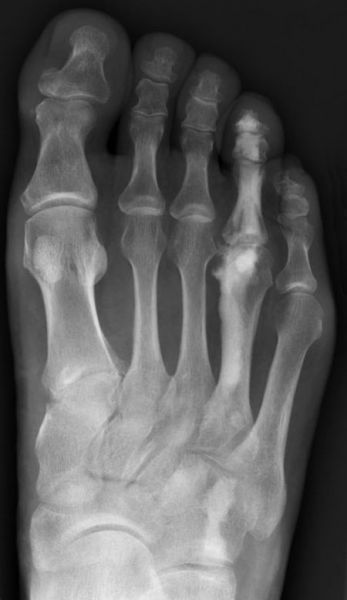

Das Enchondrom ist der häufigste Knochentumor im Bereich von Hand und Fuß und nach dem Osteochondrom der zweithäufigste gutartige Knochentumor überhaupt. Die geschlechtliche Verteilung ist ausgeglichen, Enchondrome finden sich meist bei Patienten zwischen 20-40 Jahren. Dieser chondrogene Tumor verhält sich meist asymptomatisch, kann aber durch eine Knochenexpansion und Schwellung sowie Spontanfrakturen (Abb. 17) auffallen. Radiologisch zeigen sich in der Regel gut abgrenzbare Osteolysen, Matrixverkalkungen sind typisch aber nicht obligat. Die MRT zeigt typischerweise eine annähernd flüssigkeitsäquivalente Signal­qualität mit niedrigen Signalintensitäten in T1 und hoher Signalgebung in T2, die Binnen­struktur weist eine für chondrogene Tumoren typische Lobulierung mit KM-Aufnahme auf.

Im Gegensatz zu Osteochondromen ist die Lage von Enchondromen nicht auf die Metaphyse beschränkt. Sie finden sich auch im Bereich der Epi- und Diaphysen. Die kurzen tubulären Knochen der Metatarsalia und Phalangen sind bevorzugt betroffen. Hier findet sich die Läsion typischerweise im Bereich der proximalen Phalangen oder distalen Metatarsalia, eine Ausbreitung auf die gesamte Diaphyse ist von hier aus jedoch nicht ungewöhnlich. Die Möglichkeit einer malignen Entartung (Chondrosarkom) ist im Bereich der Metatarsalia und Phalangen im Vergleich zu den langen Röhrenknochen und platten Knochen extrem selten 33. Die übliche Therapie besteht in einer gründlichen Curettage. Je nach Größe des Defekts und Schwächung der Kortikalis kann die Transplantation eines stabilisierenden kortiko­spongiösen Spans notwendig werden. Zusätzliche osteosynthetische Verfahren sind nur selten erforderlich.